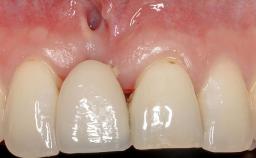

A 30-year-old woman was referred by her general dentist for evaluation of an esthetic complication related to previous implant treatment for congenitally missing maxillary lateral incisors. The patient’s chief complaint was the inadequate esthetic appearance of her smile. The case demonstrates the use of a combined approach to achieve optimal results. Two different flap designs - a tunnel technique and a coronally advanced flap - are employed based on the surgical objectives for the affected site.

Soft Tissue Grafting Yes

Soft Tissue Anatomy Intact Defective